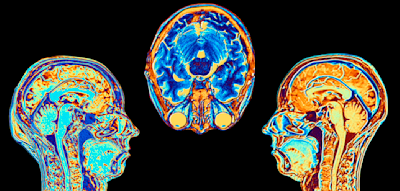

Ärzte hatten bei ihr Ende Januar Blutkrebs festgestellt, Leukämie ist dabei die häufigste Form. In Deutschland erhält alle zwölf Minuten ein Mensch diese Diagnose. Für viele Betroffene ist eine Stammzellspende die letzte Chance auf ein Überleben, so vielleicht auch für Cinja.